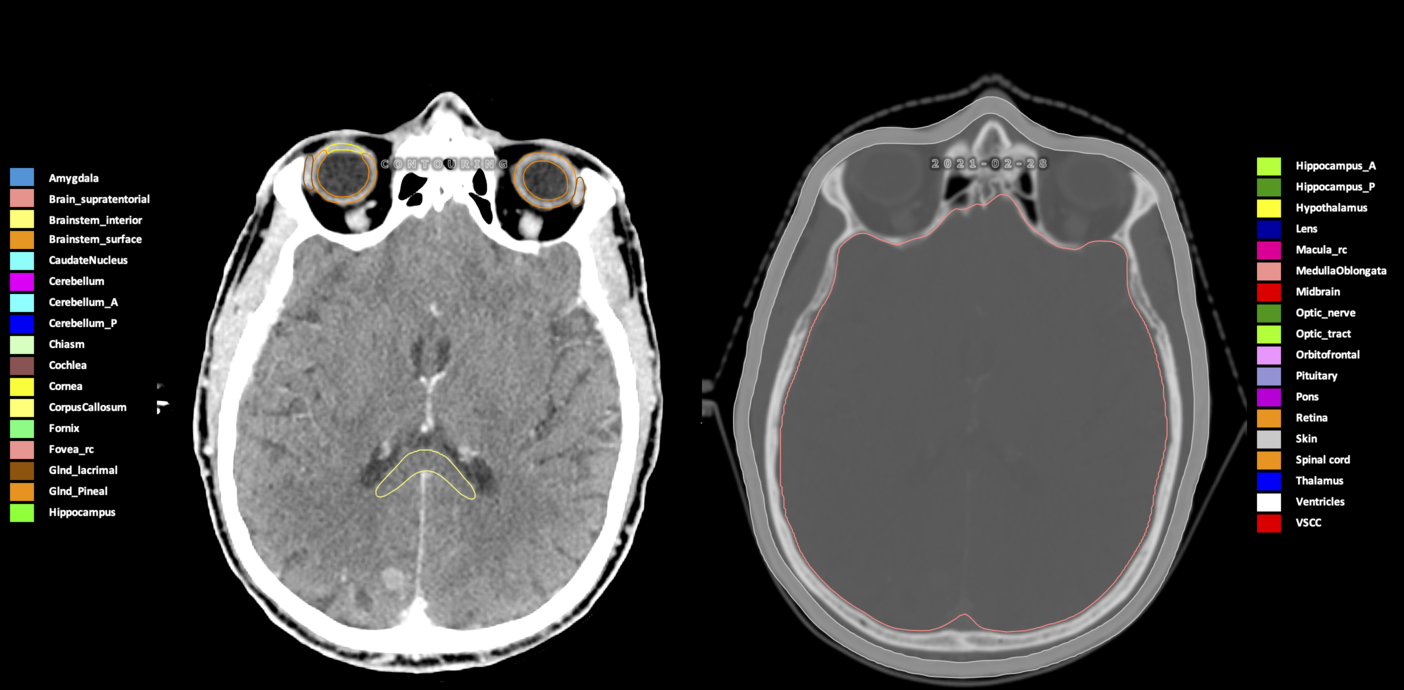

Included are all OARs known to be relevant for radiation-induced toxicity in neuro-oncology: brain, brainstem (midbrain, pons, medulla oblongata), chiasm, cerebellum (anterior & posterior), cochlea, cornea, hippocampus (anterior & posterior), hypothalamus, lens, lacrimal gland, optic nerve, pituitary, skin, and vestibular & semicircular canals. To further facilitate research on cognition, vision and radiological changes after irradiation of the brain, potential clinically-relevant OARs are included: amygdala, caudate nucleus, cerebellum (anterior & posterior), corpus callosum, fornix, macula, optic tract, orbitofrontal cortex, periventricular space (PVS), pineal gland, and thalamus.

Three-dimensional delineation of the 25 consensus OARs for neuro-oncology are shown on CT (WW/WL 120/40, 3000/600), 3T MR images, (T1Gd, T2FLAIR 1mm) and 7T MR (MP2RAGE 0.7 mm). All are presented in transversal, sagittal and coronal view.